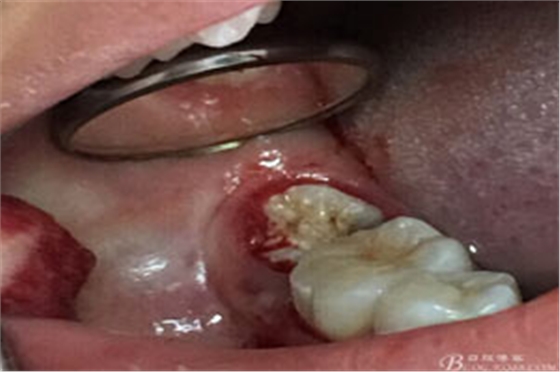

圖3.取出棉球口內(nèi)發(fā)現(xiàn)37合面有開髓孔,探針出血,頰側(cè)牙齦紅腫